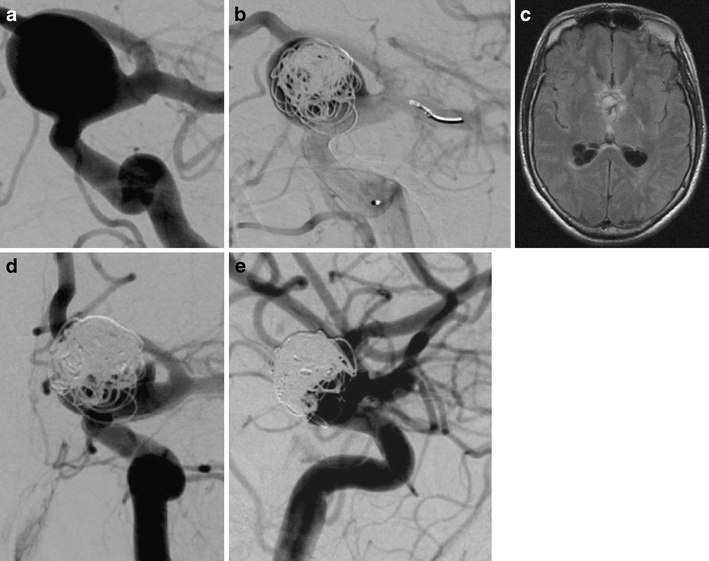

Figure 1 from Use of coils in conjunction with the pipeline What Is The Cpt Code For Pipeline Embolization There are no hcpcs device c codes for embolization beads. The pipelinetm flex embolization device is indicated for the endovascular treatment of adults (22 years of age or older) with large or giant. There are no hcpcs device c codes for embolization beads. Pipeline embolization device and treatment of brain aneurysms. Reimbursement is included in the procedural payment. Reimbursement is. What Is The Cpt Code For Pipeline Embolization.